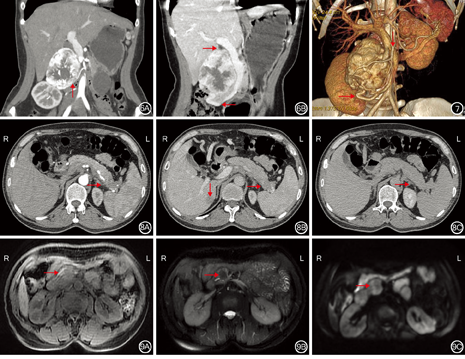

20例功能性pNENs患者,肿瘤直径为0.6~3.0 cm,平均肿瘤直径为1.5 cm。肿瘤部位:胰头部4例,胰体部10例,胰尾部6例。20例功能性pNENs患者中,19例肿瘤边界清楚,1例肿瘤边界欠清晰。20例功能性pNENs患者中,18例肿瘤密度均匀,2例肿瘤密度不均伴囊变,肿瘤均不伴有钙化。20例行动态增强扫描:19例肿瘤动脉期强化明显,门静脉期及延迟期强化程度稍高或等于正常胰腺组织,1例肿瘤动脉期呈弱强化、门静脉期及延迟期强化程度等于或稍低于正常胰腺组织。见图1。3例患者行MRI扫描检查患者:肿瘤均表现为脂肪抑制T1加权成像呈低信号,T2加权成像呈高信号,DWI(b=1 000 s/m2)高信号,肿瘤显示清晰。见图2。20例患者中,1例伴有肿瘤远端胰腺组织萎缩、胰管扩张、多发潴留囊肿及肝总动脉旁淋巴结肿大(图3)。

13例无功能性pNENs患者,肿瘤直径为1.5~16.0 cm,平均肿瘤直径为5.0 cm。肿瘤部位:胰头部6例,胰腺钩突部1例,胰体部3例,胰尾部3例。13例无功能性pNENs患者中,11例肿瘤边界清晰,2例边界不清晰。13例无功能性pNENs患者中,3例肿瘤密度较均匀,10例密度不均,伴有囊变(图4)。13例无功能性pNENs患者中,2例肿瘤伴有钙化(图5)。13例行动态CT增强扫描患者:其中12例肿瘤动脉期强化明显,门静脉期及延迟期持续性强化,囊变区强化不明显,部分肿瘤可见明显增粗的供血动脉及引流静脉(图6, 图7);1例肿瘤强化较弱,三期强化程度均稍低于正常胰腺组织,边界不清晰(图8)。6例患者行MRI扫描检查,4例患者肿瘤脂肪抑制T1加权成像呈低信号,T2加权成像呈稍高或混杂信号,DWI(b=1 000 s/m2)呈高信号;2例患者肿瘤脂肪抑制T1加权成像呈低信号,T2加权成像呈低信号,DWI(b=800 s/m2)呈稍高信号(图9)。13例无功能性pNENs患者中,4例出现胆管及胰管扩张(图10,图11)。7例无功能性pNENs患者出现局部组织侵犯或远处转移(肝脏转移4例、胰腺周围淋巴结转移1例、肝脏和胰腺周围淋巴结同时转移1例,肝脏转移及脾动静脉侵犯1例),其中G1级1例,G2级4例,G3级2例。5例肿瘤直径>5.0 cm患者中,4例出现肝脏或淋巴结转移。